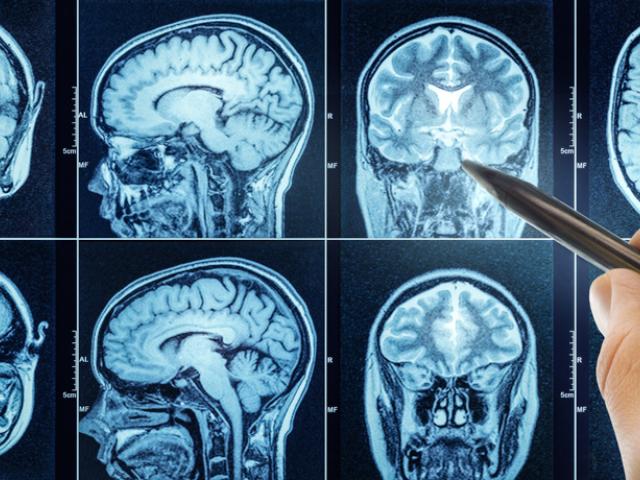

Trastornos Neurocognitivos

Le ofrecemos información acerca de los transtornos neurocognitivos, tales como el Alzeihmer y la demencia.

La demencia, dentro de la que se encuentran enfermedades como la enfermedad de Alzheimer, afecta a decenas de millones de personas en todo el mundo, según resalta la Organización Mundial de la Salud.